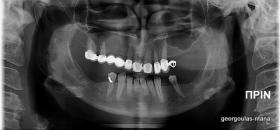

ΑΝΟΙΚΤΗ ΑΝΥΨΩΣΗ ΙΓΜΟΡΕΙΟΥ Κ ΤΟΠΟΘΕΤΗΣΗ 3 ΕΜΦΥΤΕΥΜΑΤΩΝ

Στην ασθενή αυτή πραγματοποιήθηκε ανοικτή ανύψωση ιγμορείου άνω αριστερά. Σε πρώτη φάση πραγματοποιήθηκε η οστική αύξηση και 6 μήνες μετά τοποθετήθηκαν 3 εμφυτεύματα. Τόσο στην πανοραμική όσο και στην τομογραφία κωνικής δέσμης (CBCT) που πραγματοποιήθηκαν 6 μήνες μετά την ανύψωση είναι εμφανής ο σχηματισμός οστού. Η τελευταία ακτινογραφία και φωτογραφία λήφθηκαν 5 χρόνια μετά την προσθετική αποκατάσταση.